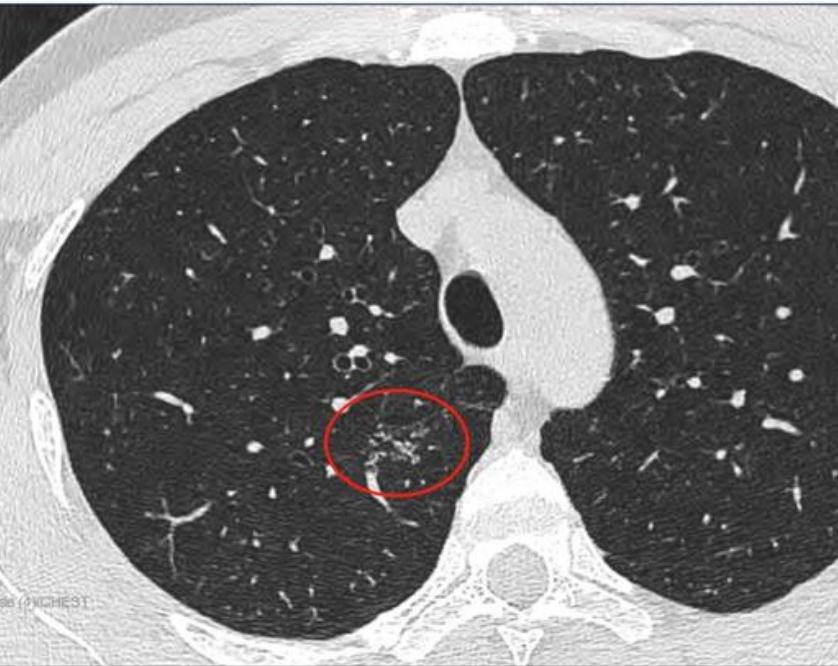

2022年7月29日去同一家A医院复查拍CT,检查结果如下,四个月后,结节从1.2变成了1.9 cm,发现结节长这么快,真的很慌,我老公不抽烟不喝酒,身体一直比较健康,没有住过院都,也没有家族史,不知道一下就长这么大一个结节,求助各位病友,各位医生,还有敬爱的戴主任,麻烦各位有经验的帮忙看看,我们目前只看上一个北京三甲医院普通号的大夫,大夫只说磨玻璃不应该长这么快,长的挺奇怪,不典型,其他没说什么,还没挂上其他医院的号,先麻烦各位帮忙看看,万分感谢!

CT截图: